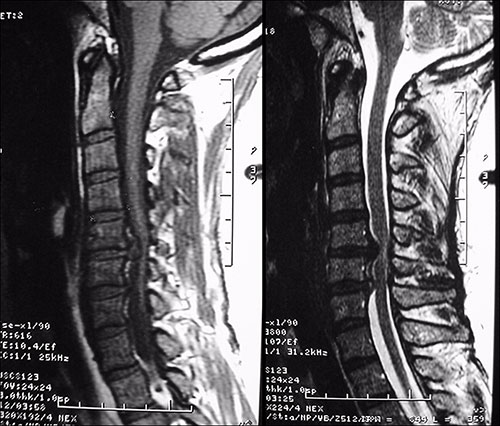

Dentre os exames de imagem, a ressonância magnética (RM) é o exame de escolha para avaliação da compressão radicular (Fig. 2). Entre as inúmeras vantagens do método é possível citar: exames contrastantes em T1 e T2, sem uso de radiação ionizante, ótima definição das estruturas neurais e das partes moles (Fig. 5). Quando a RM não for disponível, a tomografia computadorizada (TC) ou a mielotomografia (realizada com contraste) podem ser úteis (Fig. 3).

Fig. 5. Hérnias de disco C5-C6 e C6-C7 vistas na RM, exame ponderado em T1 a esquerda e T2 a direita.

Fig. 3. Mielotomografia demonstrando alterações degenerativas e estenose do canal cervical